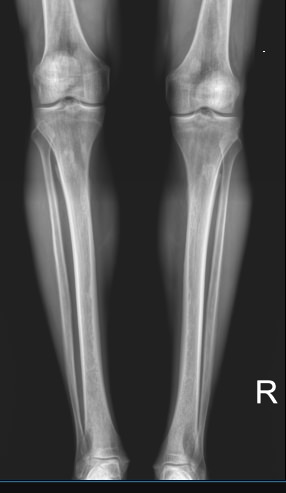

Большая берцовая кость ― вторая по толщине после бедренной ― вместе с малоберцовой образует часть нижней конечности ― голень. Она принимает на себя вес человека, позволяя ему свободно передвигаться и поднимать значительные грузы. Для повреждения голеней требуется значительная сила, какая встречается, например, при ДТП. С другой стороны, хронические патологии обеих костей, а также прилегающих к ним суставов, медленно и незаметно наносят не меньший вред, лишая мобильности.

При первых признаках заболеваний или травмы лучше проконсультироваться со специалистом и приступить к лечению на ранней стадии. Ортопед, травматолог или онколог направляют на рентген обеих голеней, если необходимо сравнить состояние симметричных участков, при травме или хронической патологии и при подозрении на аномалии развития. Выбор данного вида диагностики вызван простотой и доступностью методики, ее безболезненностью для пациента и высокой информативностью для врача.

Что покажет рентген костей голени обеих ног

• Изменения в мягких тканях: инородные тела, осколки, отеки;

• Патологии суставов, вошедших в снимок: вывихи и воспалительные процессы;

• Переломы костей: их расположение, уровень заживления и степень консолидации, соответствие сроку травмы;

• Состояние костной ткани: подозрение на онкологические изменения, остеопороз, остеосклероз, остеонекроз;

• Состояние надкостницы: истончение или утолщение.